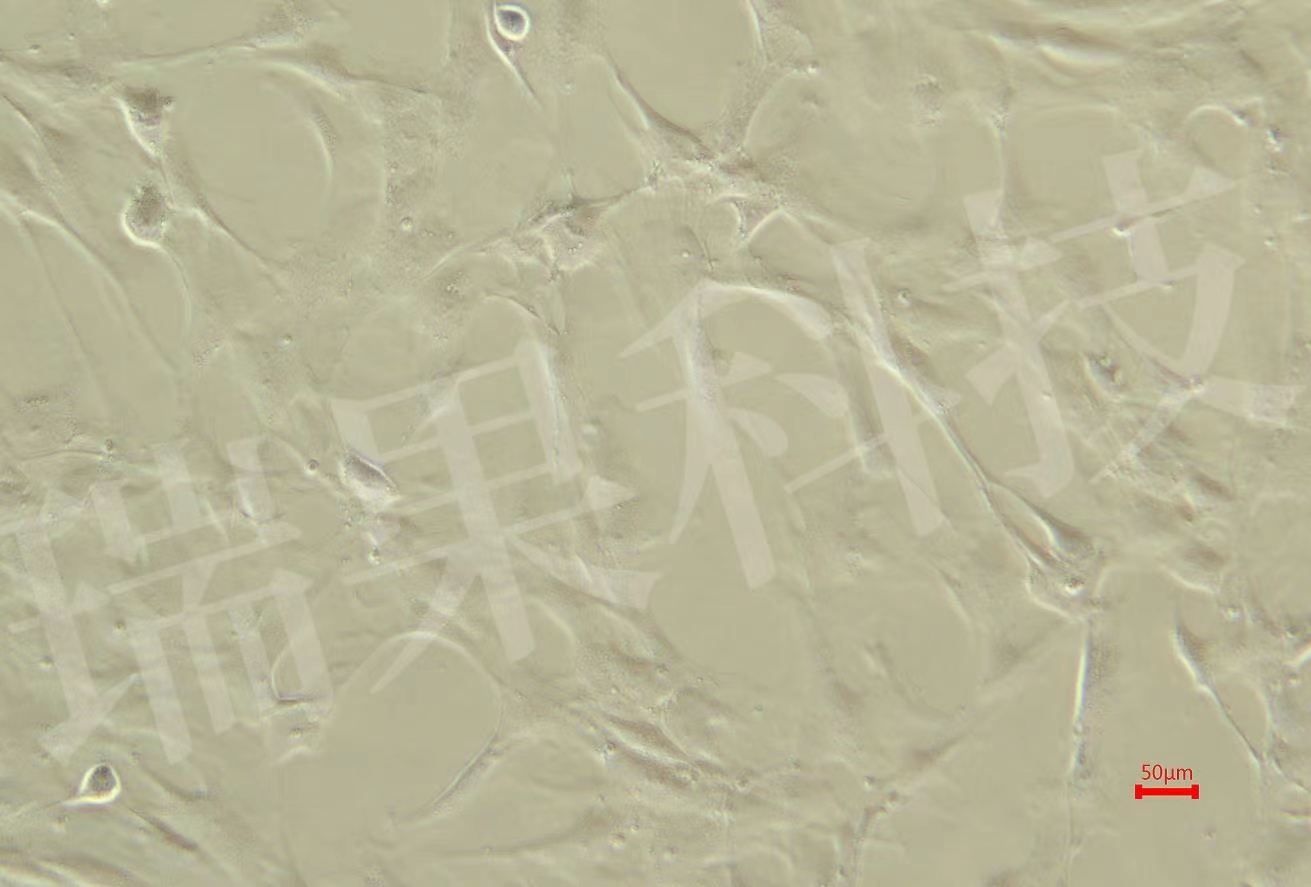

rRMEC